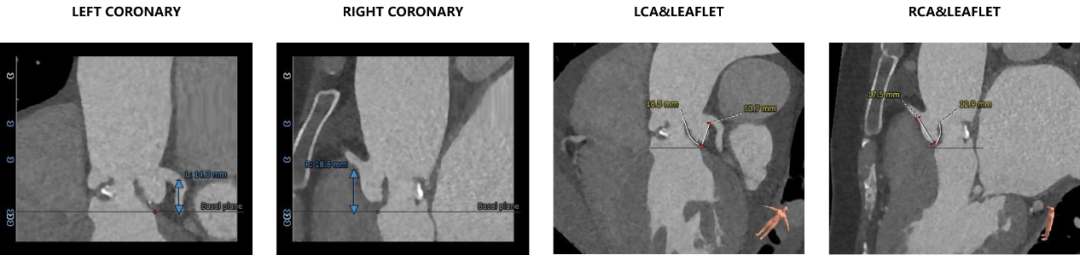

1.主动脉瓣瓣环周长86.9mm,平均周长径27.6mm。

2.主动脉瓣呈三叶式,瓣叶纤维增厚,瓣叶粘连严重,钙化散在分布。

3.左右冠脉开口高度可,冠状动脉内径较粗,左冠瓣长度大于冠脉开口至瓣叶附着缘距离。

4. 主动脉瓣环与水平面夹角可,主动脉弓角度与宽度可。入路血管局限少量钙化,双侧血管内径良好,整体入路血管条件尚可。

瓣叶纤维化增厚严重,左冠瓣长度大于冠脉开口至瓣叶附着缘距离,左侧冠脉有一定堵塞风险。

该病例少量钙化,合并主动脉瓣中度反流,瓣膜锚定难度偏高,有瓣膜位移风险。需采用较高位(瓣环下0-2mm)释放策略,释放位置需精准。

1.该病例主动脉瓣瓣环平均径、周长径数值位于瓣膜推荐型号AV29至AV31型号之间,需综合考虑左侧冠脉阻塞风险和瓣膜位移风险,术中需通过主动脉根部造影和球囊预扩确定瓣膜尺寸。

2.患者瓣叶增厚严重,左冠瓣长度大于冠脉开口至瓣叶附着缘距离,存在冠脉阻挡风险,术中需根据球囊预扩情况决定是否做冠脉保护。

3.根据术前CT评估,跨瓣角度为LAO 5° CAU 5°(右窦中心位)。球囊预扩角度为LAO 5° CRA 5°(右窦中心位),释放角度为RAO 25° CAU 29°(左右窦重合)。使用25mm球囊预扩,根据沛嘉TaurusElite®产品设计特点采取瓣环平面下0-2mm高度释放策略。